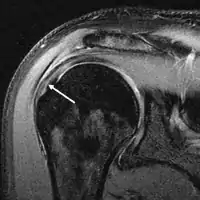

A complete tear of the supraspinatus resulting in a shift upwards of the head of the humerus

Diagnosis is based upon physical assessment and history, including description of previous activities and acute or chronic symptoms. A systematic, physical examination of the shoulder comprises inspection, palpation, range of motion, provocative tests to reproduce the symptoms, neurological examination, and strength testing.[28] The shoulder should also be examined for tenderness and deformity. Since pain arising from the neck is frequently 'referred' to the shoulder, the examination should include an assessment of the cervical spine looking for evidence suggestive of a pinched nerve, osteoarthritis, or rheumatoid arthritis.

Diagnostic modalities, dependent on circumstances, include X-ray, MRI, MR arthrography, double-contrast arthrography, and ultrasound. Although MR arthrography is currently considered the gold standard, ultrasound may be most cost-effective.[31] Usually, a tear will be undetected by X-ray, although bone spurs, which can impinge upon the rotator cuff tendons, may be visible.[32] Such spurs suggest chronic severe rotator cuff disease. Double-contrast arthrography involves injecting contrast dye into the shoulder joint to detect leakage out of the injured rotator cuff[33] and its value is influenced by the experience of the operator. The most common diagnostic tool is magnetic resonance imaging (MRI), which can sometimes indicate the size of the tear, as well as its location within the tendon. Furthermore, MRI enables the detection or exclusion of complete rotator cuff tears with reasonable accuracy and is also suitable to diagnose other pathologies of the shoulder joint.[34]